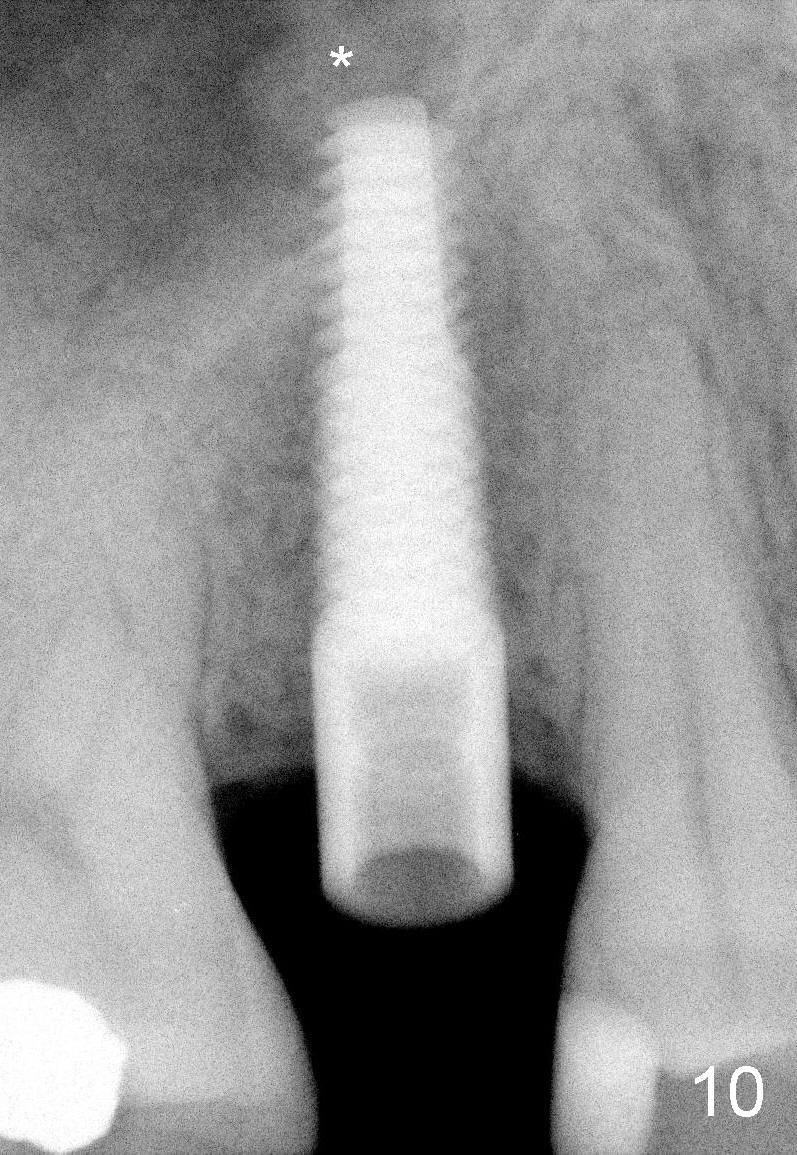

Nine months later, the patient returned for re-implantation (Fig.7). Amoxicillin and Chlorhexidine were used preop and postop. Flaps were raised for better vision of reimplantation site (Fig.8). Bone density was high (type II). Drills were used to form osteotomy (Fig.9). A 4x17 mm implant was placed with internal sinus lift (Fig.10*). The insertion torque was also >60 Ncm. The flaps were approximated and a short abutment (Fig.11 A) was placed to hold perio dressing in place.

X-ray at 2.5 months postop shows crestal bone loss (Fig.12 *), although the implant is stable without inflammation (Fig.13 C: healing cuff). When the crown is bonded 3.5 months postop, there is no papilla (Fig.14 *).